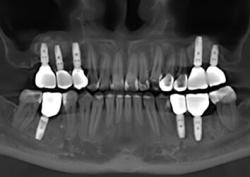

Примеры работ синус-лифтинга

Ежедневно мы восстанавливаем улыбку и уверенность в себе 5–7 пациентам.